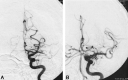

Background and purpose: We evaluated a mechanical thrombectomy protocol to treat acute stroke and report the angiographic results and clinical outcomes.

Methods: Patients with anterior circulation strokes <8 hours and posterior circulation strokes <12 hours were treated at a single center over 10 months. Patients were excluded if they were candidates for intravenous tissue plasminogen activator (tPA). Treatment involved one of two mechanical thrombectomy devices. Retrieval was augmented by low-dose intra-arterial tPA if needed. Outcome was measured by using the Modified Rankin score.

Results: Ten patients were treated: five with anterior circulation strokes, four with posterior circulation strokes, and one with embolic strokes involving both circulations. Mean National Institutes of Health Stroke Scale score at presentation was 24.6 +/- 10.9. In eight patients (80%), revascularization was successful (Thrombolysis in Acute Myocardial Infarction score, 3). Mean time from symptom onset to initiation of the procedure was 6 hours (5.3 hours for anterior circulation and 7.0 hours for posterior circulation). Mean time for recanalization from the start of the procedure was 1.17 +/- 0.58 hours for the six anterior circulation strokes and 2.75 +/- 1.34 hours in the two posterior circulation strokes. Five patients died within 48 hours; all had posterior circulation strokes. Mean Modified Rankin score at 90 days was 1.4.

Conclusion: In this small series, mechanical thrombectomy of acute stroke appeared to improve recanalization rates compared with intra-arterial thrombolysis. No hemorrhagic complications occurred. Further study is required to determine the role of these techniques.